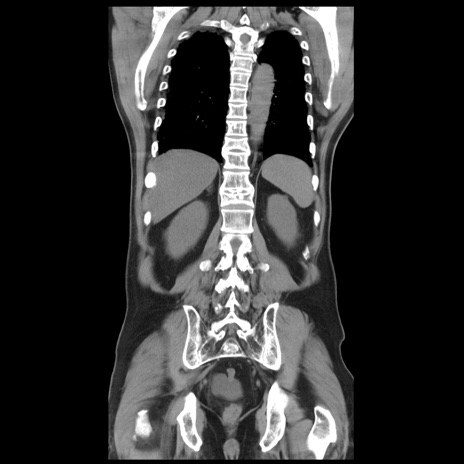

症例20(冠状断像)

【症例】 60歳代男性

【主訴】 腹部膨満、嘔吐

【現病歴】5日前頃より倦怠感を認め食事量減少し4日前の朝嘔吐、食事摂取困難となった。 3日前近医受診し点滴施行され整腸剤などを処方された。 当日他院を受診し、腹部膨満著明、炎症反応の上昇(CRP10.8、WBC11200)あり、紹介受診となる。

【身体所見】 意識JCS1 受け答えがはっきりしないBP 111/57mHg、 P 67bpm、、BT35.2°C、SpO2 97%(RA)、 腹部:膨隆、打診で鼓音あり、全体的に圧痛有り、腸蠕動音(-)、反跳痛ははっきりせず。

【データ】WBC 11400、CRP 14.20